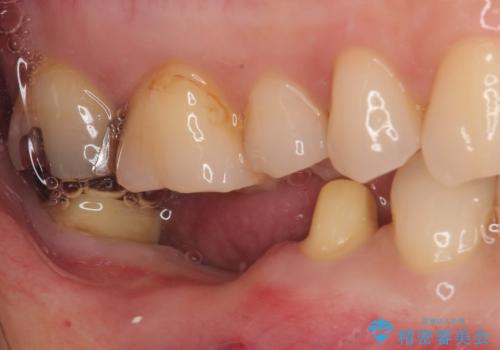

クラウンを外したところ、目視でも確認できる破折線が認められたため、抜歯することとしました。

抜歯後も膿の出口が消えず、一番奥の歯を診察したところ神経組織の反応がなかったため、根管治療を行うこととしました。

再度の歯を根管治療したため、抜歯した部位の補綴治療は、強度の問題からブリッジよりもインプラントをおすすめしましたが、患者様希望によりブリッジを選択しました。

一番奥の歯は歯肉から露出している高さが少なく、クラウンを装着する不十分であったため、歯冠長延長術を行うこととしました。